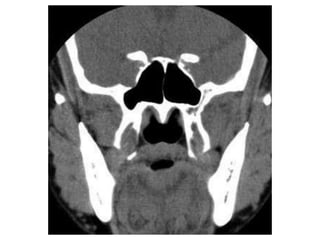

This document discusses sinus imaging using CT scans. It first describes the different sinus cavities in the anatomy: frontal, maxillary, nasal, ethmoid and sphenoid. Second, it lists common sinus pathologies seen on CT such as sinusitis, fungal sinusitis, deviated septum, sinus polyps, mucoceles, concha bullosa and sinus cancer. Finally, it presents two case studies and asks questions to test understanding of sinus conditions and anatomy.